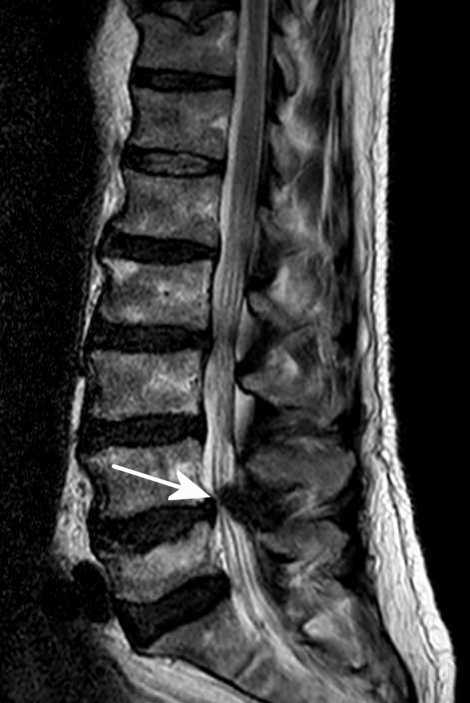

Abb.8, Abb.9: MRT-Bilder einer seitlichen Quetschung des Rückenmarks (Pfeile).

Die Rollübung zeigte bei einem Bekannten mit chronischem Hexenschuß keine Wirkung. Im MRT-Bild waren seitlich verrutschte Bandscheiben als Ursache zu erkennen. Aber zum Glück rutschte er bei Gartenarbeiten aus und fiel dabei heftig auf den Rücken. Der Schreck beim Sturz hatte vielleicht die Muskeln der Wirbelsäule so heftig angespannt, daß Bandscheiben und Wirbel durch den Sturz wieder in eine normale Lage rutschten. Der Hexenschuß ist verschwunden, er läuft seitdem wieder ohne Rollator. (Allerdings bin ich nicht sicher, ob es am Sturz lag. Er hatte vorher die Rollübung probiert und hatte sich beschwert, daß diese furchtbar schmerzhaft sei.)